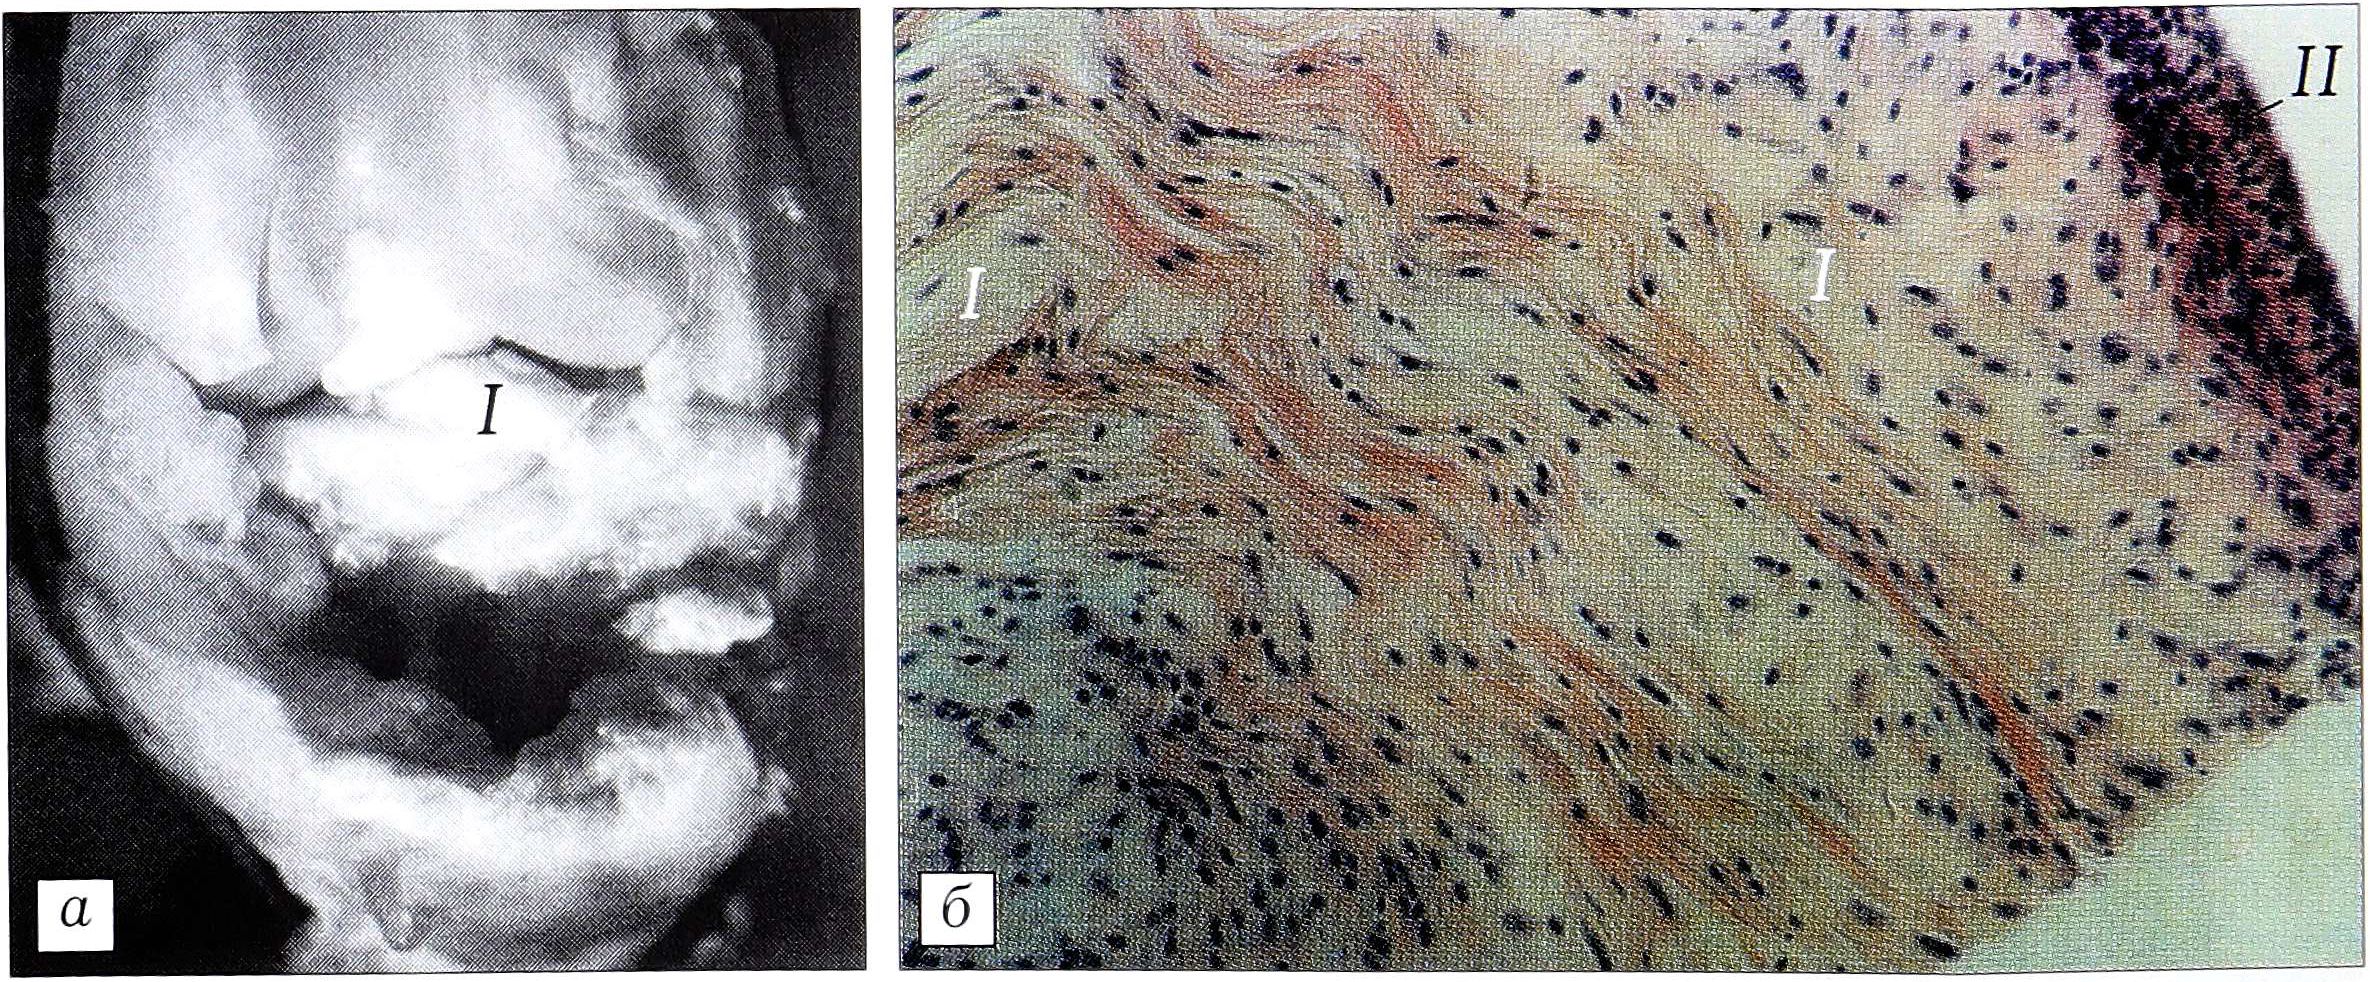

Изучены размеры ПКС у кроликов в норме: длина ее составила 6 мм, ширина — до 4 мм. Связка имеет двухпучковое строение — переднелатеральный и заднемедиальный пучки (рис. 1, а).

При морфологическом исследовании (рис. 1,б): ПКС кролика состоит из пучков коллагеновых волокон. Часть волокон в продольном направлении переходит из одного пучка в другой. Фиброзной оболочки вокруг пучков волокон практически не видно, однако отчетливо просматриваются фибробласты, расположенные рядами вдоль поверхности коллагеновых пучков. Между пучками коллагеновых волокон проходят мелкие сосуды.

Рис. 1. ПКС кролика в норме. а — макроскопически (ув. 4): связка (I) имеет пучковое строение; б — микрофотограмма (продольный срез связки): пучки коллагеновых волокон, идущие в одном направлении и разделенные рядами уплощенных фибробластов (окраска гематоксилином и эозином, ув. 10 × 20).